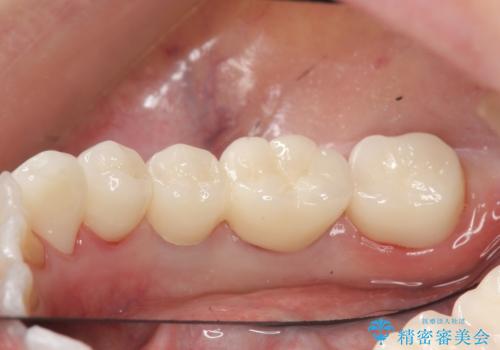

その後右下5、6番目にはインプラントを埋入し、右下3、4、5、6、7番の歯の補綴をオールセラミッククラウンによって行いました。

今回用いたオールセラミッククラウンはジルコニアフレームという白い素材の上にセラミックを盛っているため、審美性が非常に高いのが特徴です。

また、ジルコニアは人工ダイヤモンドの材料にも使われているほど高い強度を持っており、そのためオールセラミッククラウンは審美性だけでなく、奥歯やブリッジの補綴も可能とするクラウンです。